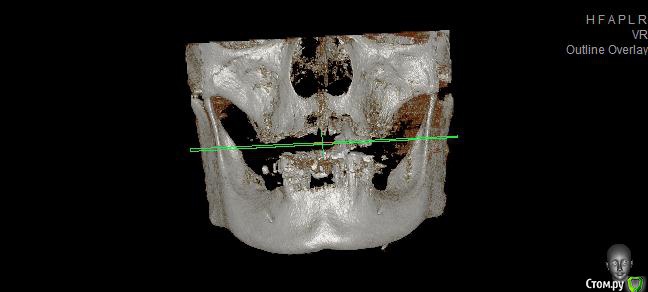

Реальная картина на сегодня:

1.        Верхняя челюсть – полная адентия (имеется один корень клык)

2.        Нижняя челюсть – протез просел – в коррекции отказано, (с левой стороны протез держится на отдельно стоящем подвижном зубе, т.к. распалось соединение с зубным рядом.)

- Нижняя челюсть выдвинулась в перед (возрастной мезиальный прикус)

- Нижняя челюсть гипермобильна , дисфункция ВНЧС, хрустит прикус прогенически,  (диагноз ЧЯХ (в лечение отказан) Рот открывается рывком (безболезненно)

3. Съёмный протез на верхнюю челюсть сделан некорректно, без учета прикуса (сточена на половину правая часть искуса), верхний протез выдвинут вперед (получился дистальный глубокий прикус), напряжение в нижней челюсти.